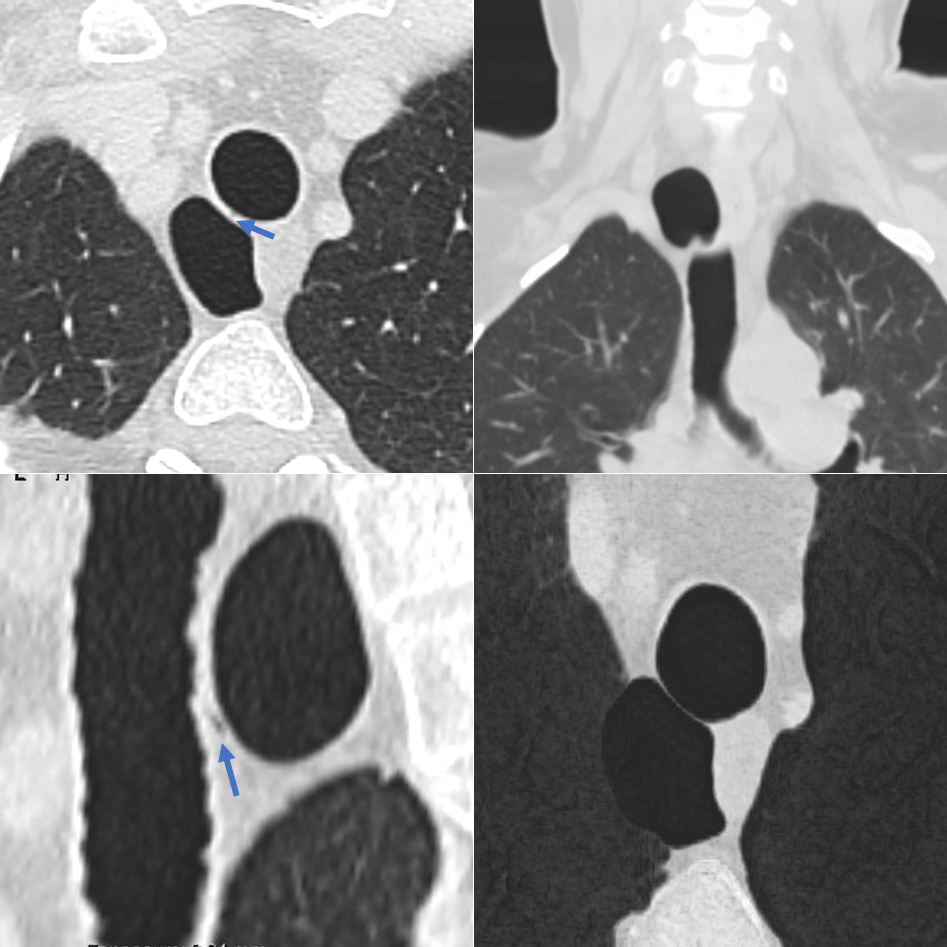

对该病变进行CT检查显示在胸廓入口处有一右后气管旁气囊。可见与气管腔相通,诊断为气管憩室。

图2 CT图像(肺窗和MinIp)显示右后外侧气管旁含气囊肿,壁薄。注意囊肿与气管连通(箭头),诊断为气管憩室。